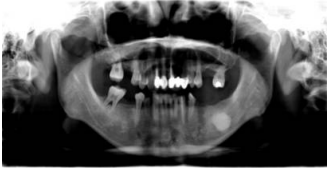

46.35歲女性因右頰無痛性腫塊6個月,至醫院求治(如下圖),咬合下顎中線往左偏移6毫米。無外 傷或其他系統性病史,觸診時腫塊質地堅硬如骨,下列何者為正確的診斷方法?

(A)電腦斷層 (B)氟-18正子攝影 (C)顳顎關節攝影 (D)TC-99骨骼掃描